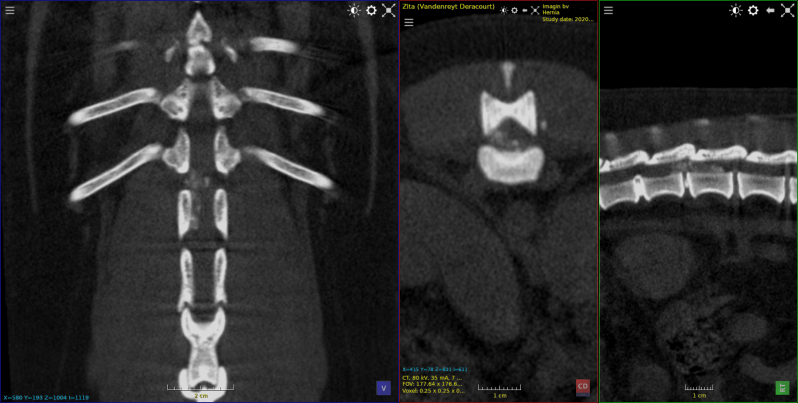

osteochondrose bij spaniel van 4 maanden

losse processus coronoideus  spaniel 4 maanden oud